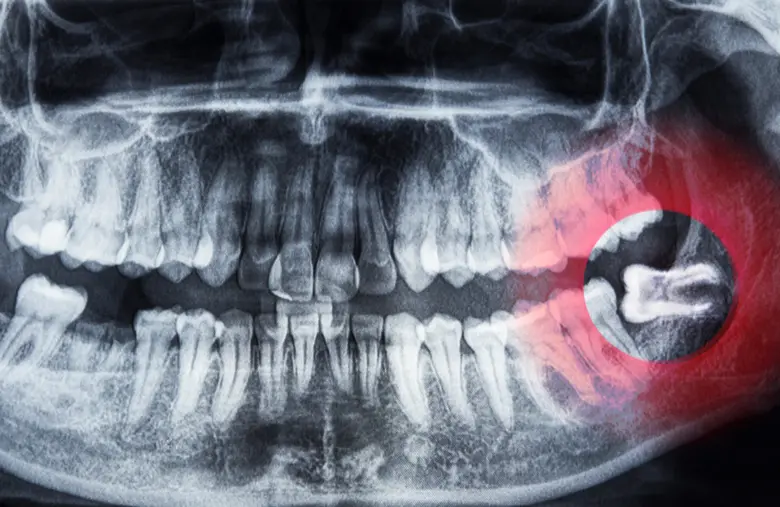

ฟันคุด คือ ฟันกรามซี่ที่สามซึ่งเป็นฟันซี่สุดท้ายที่จะขึ้นในช่องปาก โดยมักจะขึ้นในช่วงอายุ 17-25 ปี แต่ปัญหาที่พบบ่อยคือขากรรไกรมีพื้นที่ไม่เพียงพอ ทำให้การขึ้นของฟันคุดเกิดการผิดปกติในลักษณะต่างๆ ได้แก่:

• ฝังตัวอยู่ในกระดูกขากรรไกร (อาจอยู่ในแนวนอนหรือแนวเอียง โดยไม่โผล่พ้นเหงือก)